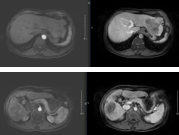

• Đánh giá đáp ứng:

Sau 1 tháng Sau 3 tháng Sau 6 tháng Sau 8 tháng

| Sau 1 tháng | Sau 3 tháng | Sau 6 tháng | Sau 8 tháng |

Hình 6. Huyết khối nhánh phải tĩnh mạch cửa | | |

Hình 7. Khối u gan phải và trái giảm kích thước (max 5,0x4,2cm) chỉ còn một phần nhỏ ngấm thuốc – Tái thông nhánh phải tĩnh mạch cửa |

| AFP: 956,0ng/mL | AFP: 113,1ng/mL AFP-L3: 22,4% Pivka-II: 689mAU/mL | AFP: 17,1ng/mL | AFP: 109,0ng/mL |

Bảng 3. Đánh giá đáp ứng điều trị bằng Sorafenib

=> Sau điều trị với Sorafenib đạt đáp ứng một phần đến tháng thứ 9 bệnh nhân chuyển sang điều trị bước 2 thuốc đích khác.